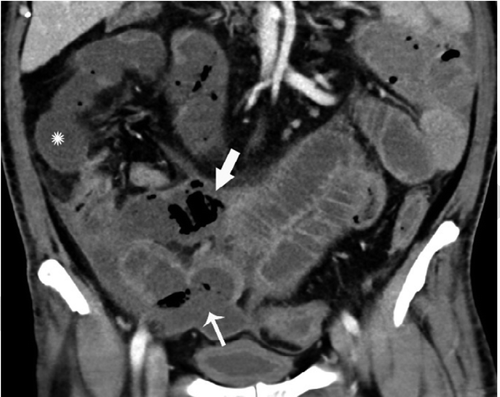

这项研究包括了412名新型冠状病毒检测阳性的患者的数据,研究人员发现,在17%的患者在治疗过程中接受腹部造影检查的患者中,近三分之一的CT扫描显示肠道异常。

“我们在COVID-19患者的影像学上发现了肠道异常,更常见的是那些去ICU的病人,”马萨诸塞州总医院的Rajesh Bhayana博士在一份声明中说。“一些研究结果是典型的缺血性肠病或肠坏死。在那些做了手术的患者中,我们看到肠坏死部位旁边的小血管凝块。ICU中的患者可能因为其他原因导致肠缺血,但我们知道COVID-19会导致凝血和小血管损伤,所以肠道可能也会受到影响。”

这项研究并没有定论,也没有确定COVID-19患者肠道不适的确切原因,但研究人员认为病毒攻击组织细胞上的ACE2受体的能力可能是主要因素。“ACE2的表达在肺泡上皮细胞、小肠的肠道细胞和血管内皮细胞中最为丰富,这表明小肠和血管可能容易受到SARS-CoV-2感染。”研究人员解释说。